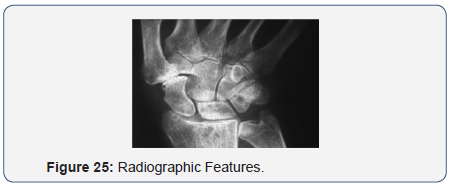

Radiographic Features

- Telescoping =14 wrists (55%)

- Accessory Ossicles = 9 wrists (40%)

- Radiological Gap = 1mm to 6mm

- Degenerative changes:

- Base of first metacarpal =14 wrists

- Distal Scaphoid = 8 wrists

- No changes =11 wrists (Figure 24).

- Residual Cartilage:

- Base of first MC -Nil in 3 wrists

- Present in 22 wrists Distal Scaphoid - Nil in 2 wrists

- Present in 23 wrists 6.Lateral subluxation of 1st MC on Abduction

- Marked subluxation in 3 wrists Moderate subluxation in 22 wrists (Figure 25).